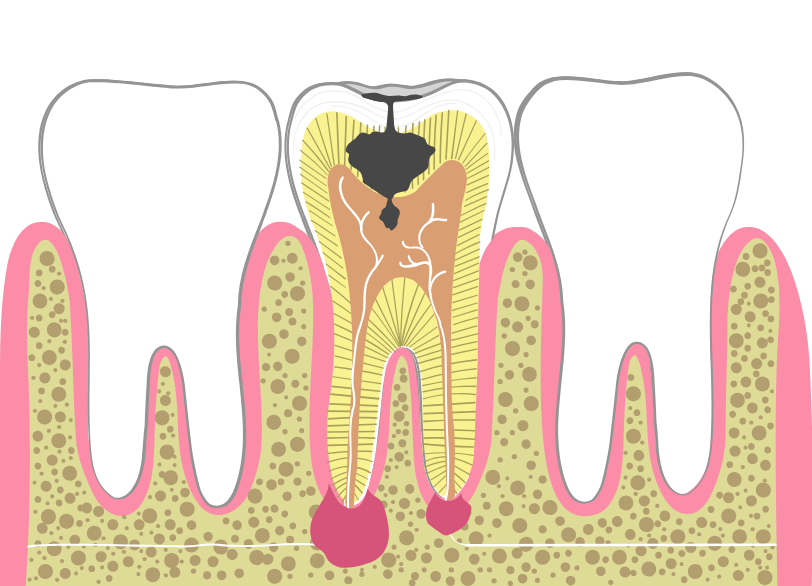

歯の内部には、神経や血管が通っている「歯髄(しずい)」と呼ばれる組織があります。

虫歯菌がエナメル質や象牙質を溶かし、この歯髄にまで到達すると、激しい炎症と痛みを引き起こします(歯髄炎)。

さらに放置すると、神経は壊死し、細菌は根の先から顎の骨へと広がり、膿の袋(根尖病巣)を作ります。

このように、細菌感染が歯の深部にまで及んだ場合、自然治癒することはありません。

感染源である神経や汚染物質を物理的に取り除き、管の中をきれいに掃除して消毒し、再び細菌が入らないように薬で密閉する必要があります。

これが根管治療です。